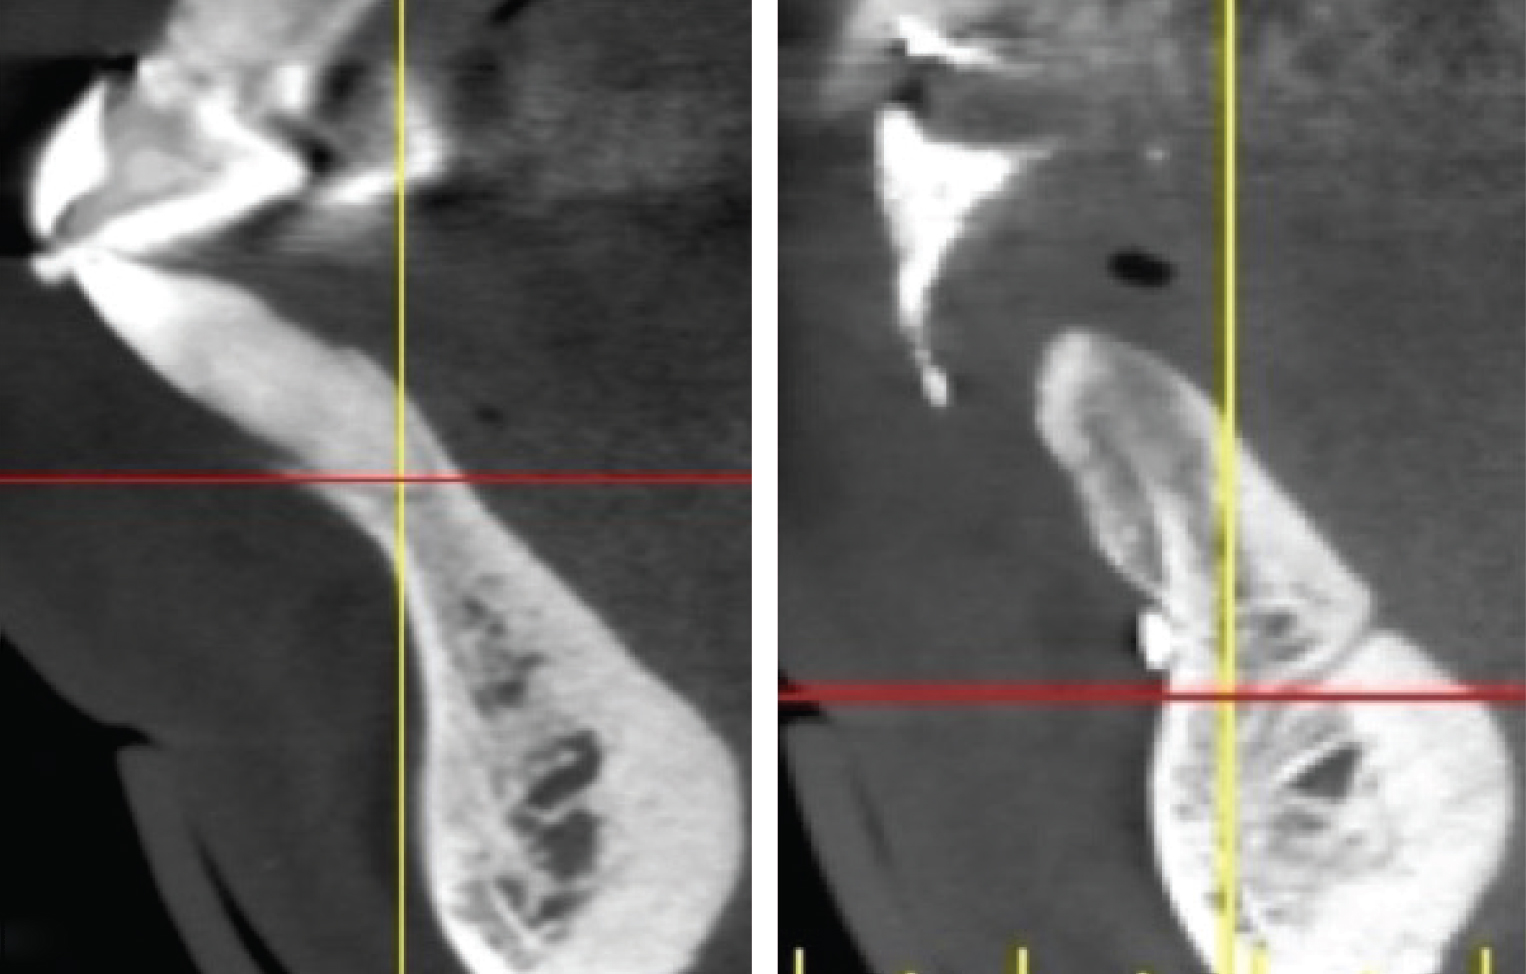

Figure 1

(Left) An example of a mandibular anterior tooth, No. 27, that was treated with extraction and replacement with a single implant. Note the concavity in the alveolus apical to the tooth. There was inadequate apical bone for extraction and immediate implant placement, thus

a 2-stage surgical approach was planned. In this case, had only the socket been  lled with grafting material there still would not have been enough bone present for proper implant placement. A full-thickness  ap was created and GBR performed to both preserve the site and correct the apical de ciency for implant placement. (Right) Note the new bone formed buccal to the ridge and the bone now available for implant placement.